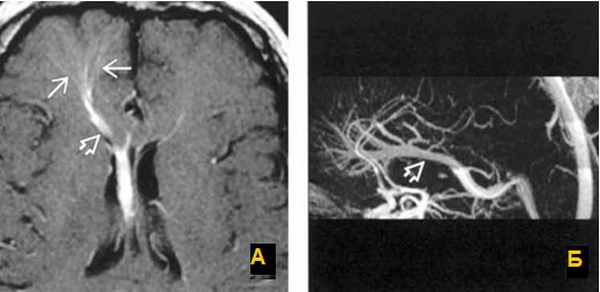

а) Т1 с внутривенным контрастированием. Стрелки показывают расширенные вены глубокого белого вещества, дренирующиеся в расширенную транскортикальную вену;

б) МР-венография с контрастированием показывает венозную дисплазию, дренирующуюся в расширенную внутреннюю мозговую вену. Венозная мальформация.